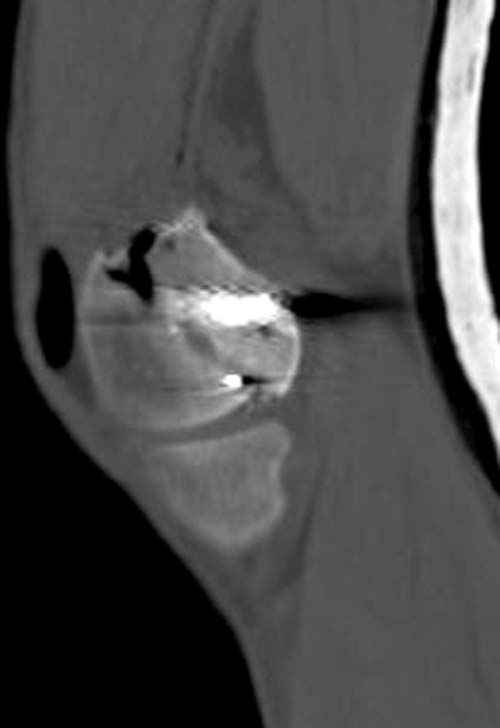

По Густило и Андерсену все high-energy переломы являются III не зависимо от степени повреждения мягких тканей. Plating такого перелома на второй день кажется немного рискованным хотя "победителей не судят". Судя по КТ, медиальный мыщелок стабильный, насколько необходимо было его фиксировать?

Идеальная репозиция?! -На снимочке A-P проeкции видна "зазубрина" по суставной поверхности, латеральный снимок - тоже не идеально.

Множество мелких FB в кости.